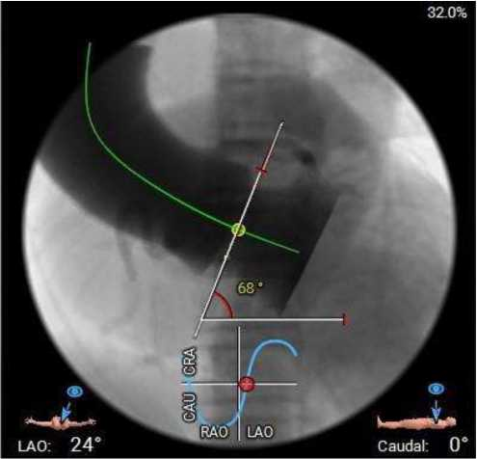

主动脉瓣环水平夹角68度,横位心,主动脉弓宽度、角度尚可,弓部存在散在钙化;

虚拟瓣环与水平夹角